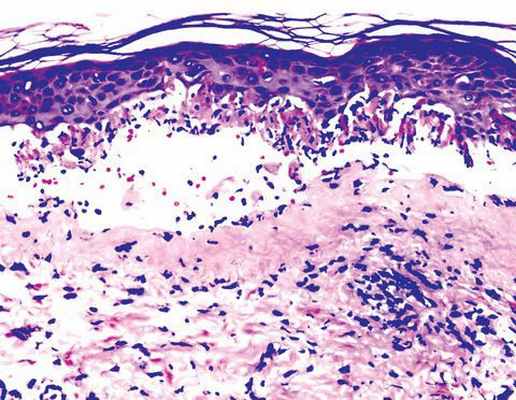

Методы исследования • Проводят лабораторные исследования для исключения сифилиса — серологические реакции, исследования на бледную трепонему • Симптомы Никольского, Асбо–Хансена отрицательны, в мазках-отпечатках нет акантолитических клеток • При гистопатологическом исследовании в эпидермисе отмечают внутри- и межклеточный отёк, гидропическую дегенерацию базальных клеток, в дерме — отёк сосочкового слоя, периваскулярные инфильтраты.

Комментарии: при гистологическом исследовании наблюдаются: отек сосочкового слоя, инфильтрация дермы различной интенсивности. Инфильтрат состоит из лимфоцитов, нейтрофилов и эозинофилов. В базальных клетках эпидермиса наблюдается вакуольная дистрофия. В некоторых участках клетки инфильтрата могут проникать в эпидермис и в результате спонгиоза образовывать внутриэпидермальные пузырьки. Вакуольная дистрофия и выраженный отек сосочкового слоя дермы могут приводить к образованию субэпидермальных пузырей.